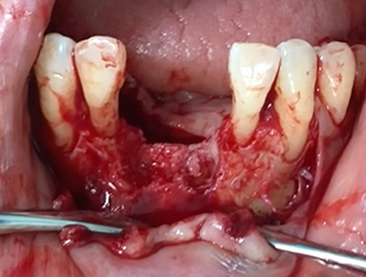

A clinical case using resorbable membrane

• A clinical case using resorbable membrane 1